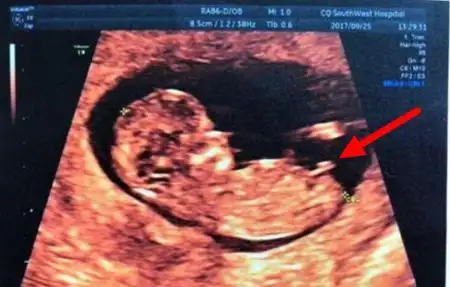

12周nt男宝特点nt值是什么nub点看男女准不准